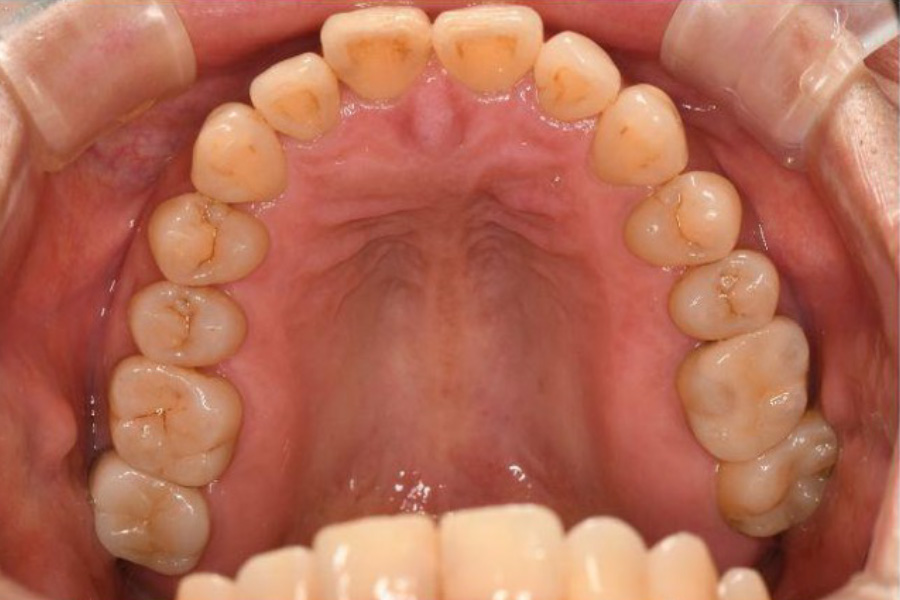

治療前